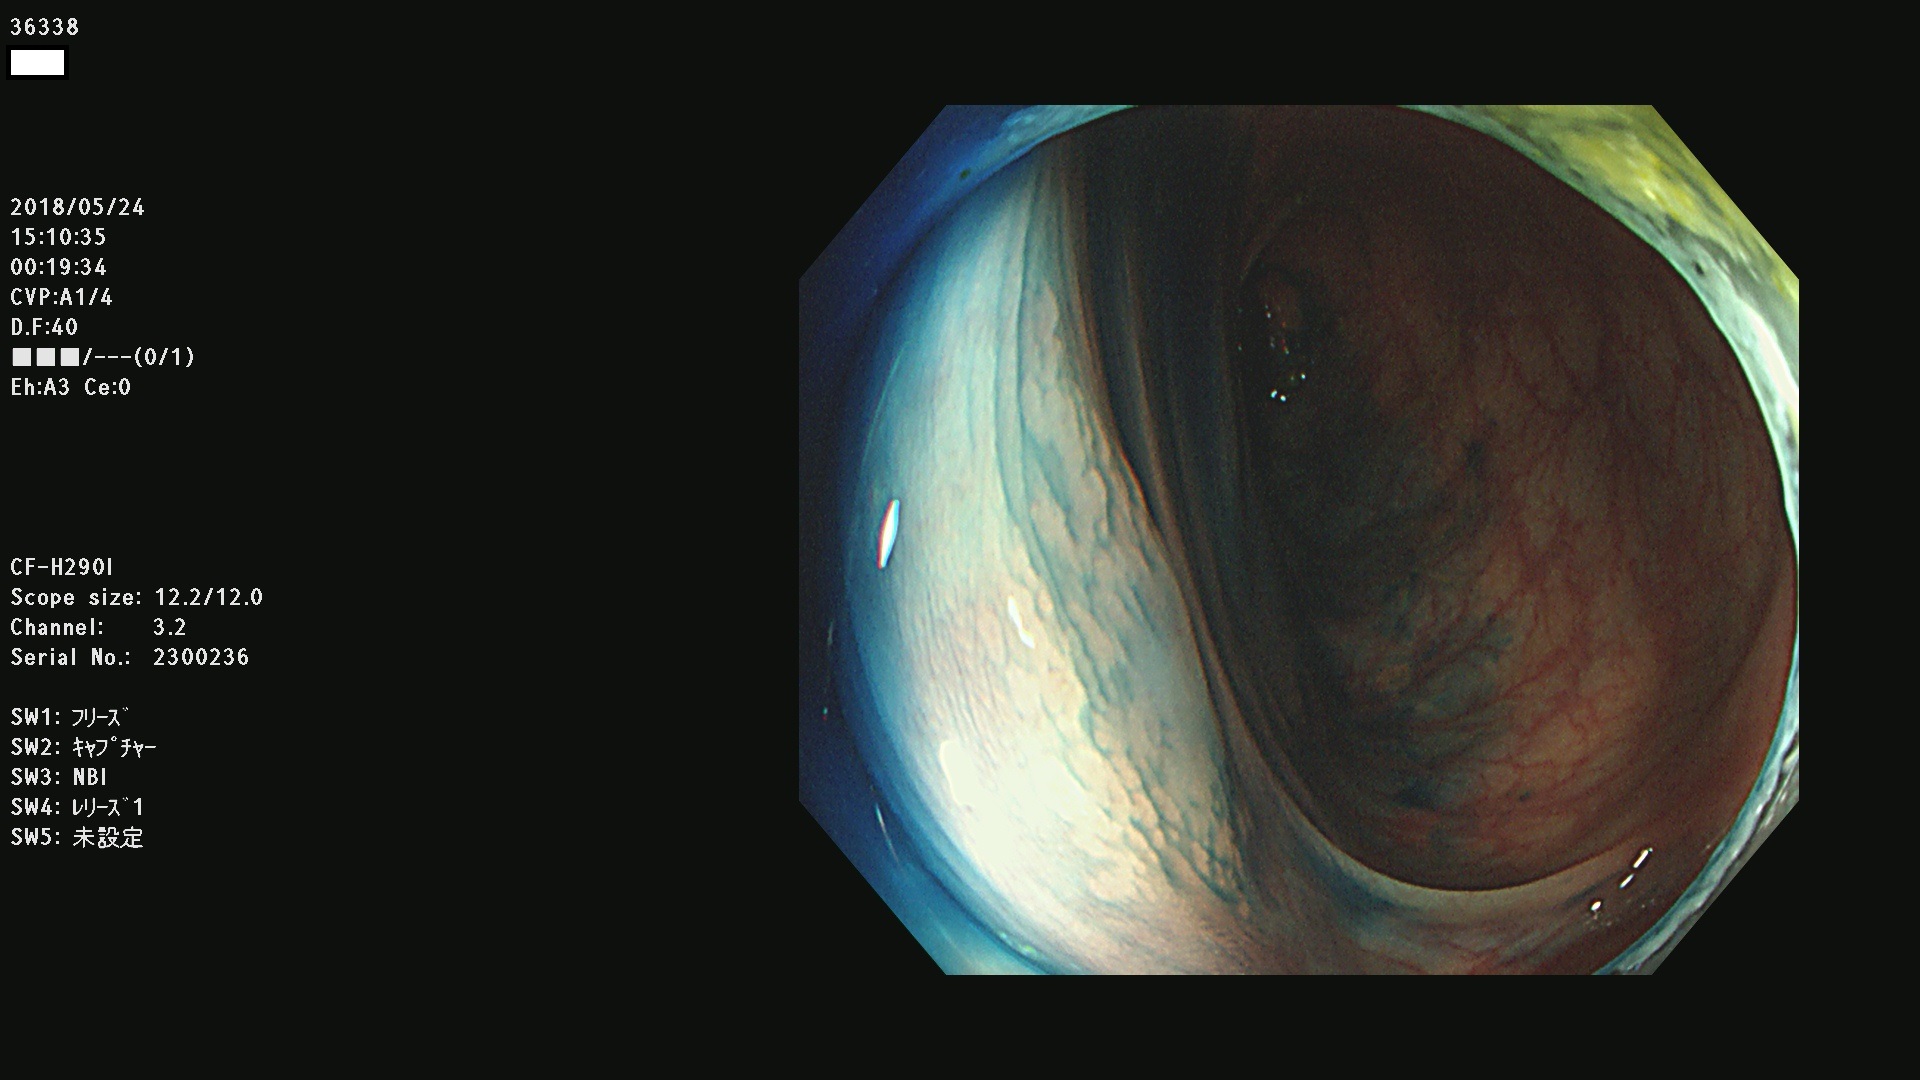

腺腫発見率 68 % (カルテ番号 36300〜36399の100名の方の検査結果で集計)大腸癌検診最新情報

以下のカルテ番号の方に腺腫(Adenoma,Group3〜5)が見つかりました(集計法)

36300 36302 36305 36306 36307 36308 36310 36311 36312 36313 36314 36315 36316 36318 36321 36322 36324 36325 36326 36327 36330 36332 36333 36334 36335(SSAPのみ) 36337 36338 36339(SSAPのみ) 36340 36341 36342(SSAPのみ) 36343 36344 36346 36348 36349 36351 36353 36354 36355(SSAPのみ) 36356 36357 36358 36359 36364 36365 36366 36367 36370 36374 36376 36379 36381 36382 36383 36384 36385 36387 36388 36389 36390 36392 36393 36395 36396 36398 36399

発見困難で危険性の高い平坦型病変(上記100名より抽出) ![]()